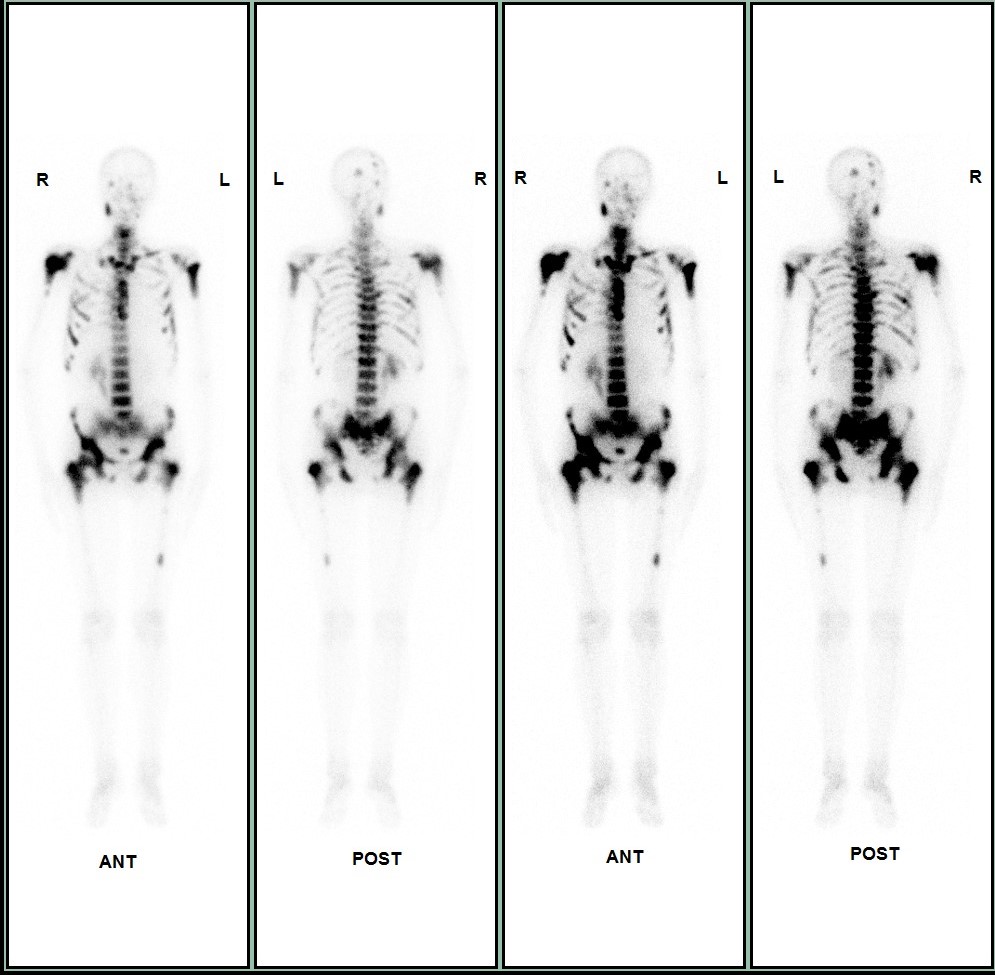

病例二 患者,男,72岁,临床确诊前列腺癌3天。全身骨显像提示:颅骨多处、双侧肩关节、双侧肱骨、胸骨、脊柱多个椎体、双侧多支肋骨、骨盆多处、双侧髋关节、双侧股骨中上段见异常显像剂浓聚影,考虑肿瘤广泛骨转移,建议行放射性核素(89锶)内照射治疗。